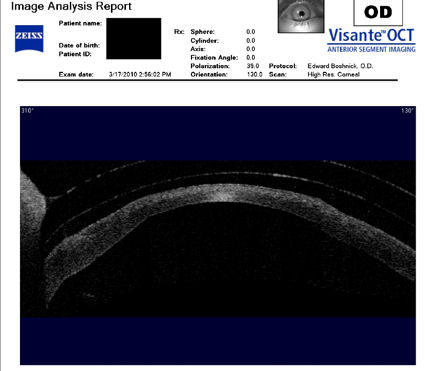

Следующие изображения были получены с использованием метода, называемого оптической когерентной томографией, или ОКТ. Прибор позволяет получить изображение в поперечном сечении путем сканирования передней части глаза (переднего сегмента) лучом света. Думайте об этом как об ультразвуке, использующем свет вместо звуковых волн для создания изображения живых тканей.

Ниже представлен снимок поперечного сечения роговицы пациента, которому был проведен RK, а затем LASIK. У пациента развилась эктазия роговицы. Красная стрелка указывает на выпячивание (эктазию).

На снимке ниже показана роговица пациента, у которого после операции LASIK развилась эктазия. Пациент носит жесткие склеральные контактные линзы. Вы можете видеть выпячивание роговицы в самом слабом месте (эктазия), что приводит к сильному искажению зрения. Очки и мягкие контактные линзы неэффективны для таких глаз, как этот. Нажмите на изображение, чтобы увеличить.

Изображения любезно предоставлены доктором Эдвардом Бошником, который посвятил свою практику восстановлению качественного зрения и информации о эктазия после операции LASIK .